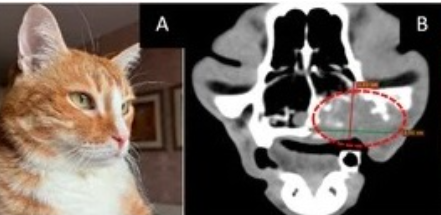

– Решение о создании Центра принято, в настоящее время приобретен компьютерный томограф. С него и начнется техническое оснащение нового исследовательского подразделения, – рассказал декан физического факультета НГУ Владимир Блинов. – В целом же на приобретение аппаратуры потребуется 200-250 миллионов рублей. Это будет уникальный, единственный в Сибири и, возможно, в России центр коллективного пользования, где будут работать представители различных сфер науки и медицины, проводя исследования на крупных животных – кошках и собаках.

Необходимость создания такого центра возникла несколько лет назад, когда начались эксперименты по определению эффективности одного из направлений лучевой терапии – бор-нейтронозахватной. Проект реализуется совместно с Институтом ядерной физики им. Г.И. Будкера СО РАН и НМИЦ онкологии им Н.Н. Блохина.

Исследования проходили по стандартной схеме: сначала на клеточных моделях, затем – на опухолевых тканях, далее – на животных моделях (мышах) иммунодефицитных линий, моделях со спонтанными опухолями. Но поскольку проект направлен на использование бор-нейтронозахватной терапии при лечении онкологии у человека, то испытаний на мелких грызунах недостаточно. Промежуточным звеном между ними должны стать крупные млекопитающие, физиология которых максимально приближена к человеческой. В данном случае – кошки и собаки со спонтанными опухолями. И тут выяснилось, что в России центров, которые проводили бы исследования на крупных млекопитающих, мало. Ученые нашли только две или три лаборатории в Москве.

– С мышами и крысами в Сибири работают многие, а вот с животными покрупнее – никто. В итоге нам пришлось взять на себя формирование групп животных для исследований, – рассказал заведующий лабораторией Владимир Каныгин. – К настоящему времени мы подвергли облучению около 40 кошек и собак с различными типами опухолей. Причем животных пришлось брать из Москвы, Санкт-Петербурга, Томска и других городов.

Иссследования проходили в Институте ядерной физики СО РАН и на учебном атомном реакторе Томского политехнического университета. Было подтверждено, что при применении нейтронозахватной терапии, и в частности бор-нейтронозахватной, в состоянии животных наблюдается положительная динамика, но говорить о гарантированном эффекте пока рано.